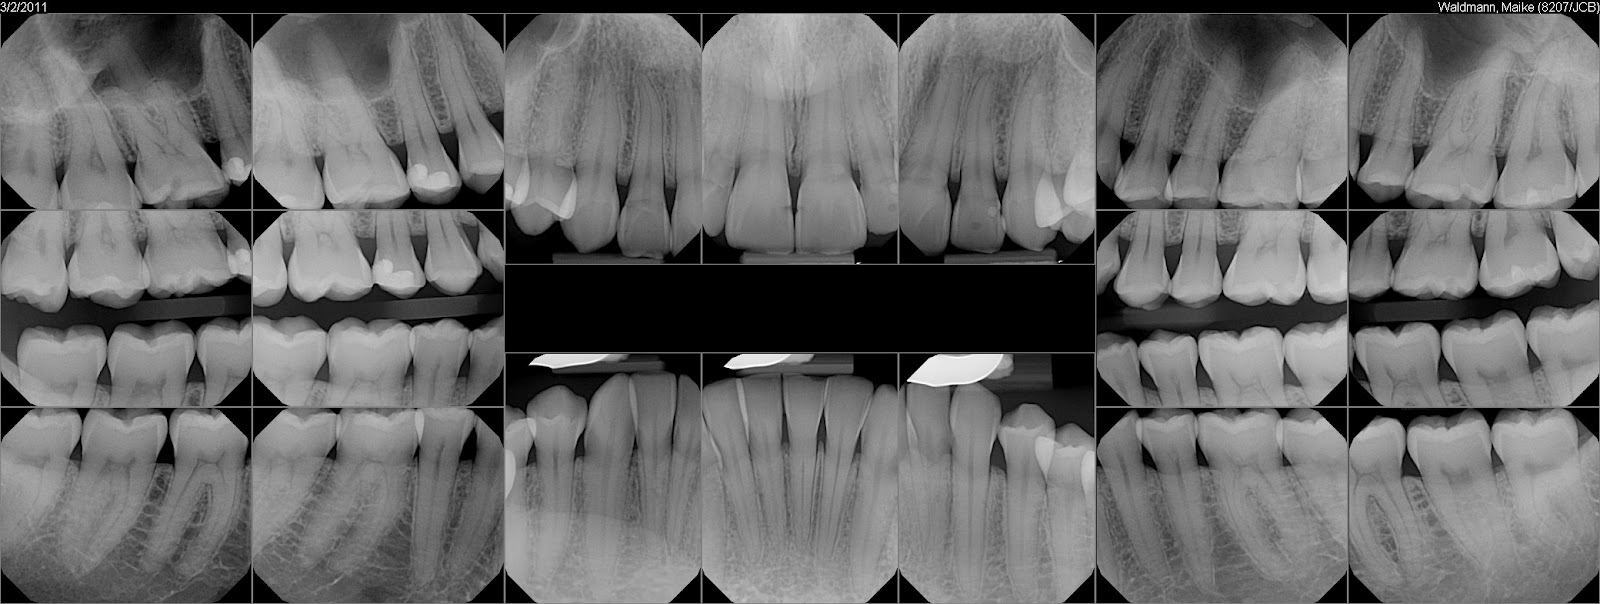

'Xrays from 3/2/2011 for use while backpacking'

- australia

Das war der Originaltext der E-Mail, die ich heute von meinem Zahnarzt bekommen habe. Schöne Bilder, nicht wahr? Meine Zähne wurden übrigens für reisetauglich befunden. Und morgen gibt es vielleicht ein paar Brain-Pics.